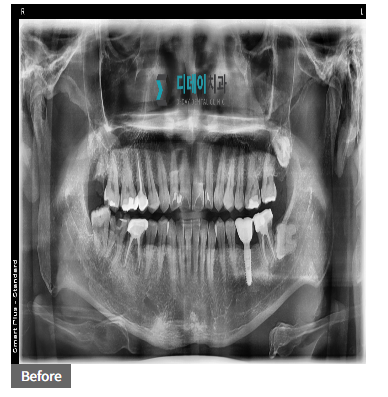

일례로, 최근에 한 40대 한자분이 내원해주셨는데요. 양쪽 아래 어금니 통증으로 급하게 치료를 받고 싶다고 하셨죠. 처음엔 원데이 임.플.란.트를 원하셨지만,

240111

진단 결과 뼈 상태가 좋지 않아 무리하게 진행하면 오히려 더 큰 문제가 생길 수 있었어요.

240422

결국 뼈 이식을 먼저 하고 일반 임플란트를 진행하기로 했습니다. 시간은 좀 더 걸렸지만,

결과적으로 더 안전하고 오래 사용할 수 있는 임플란트를 하게 되셨죠.